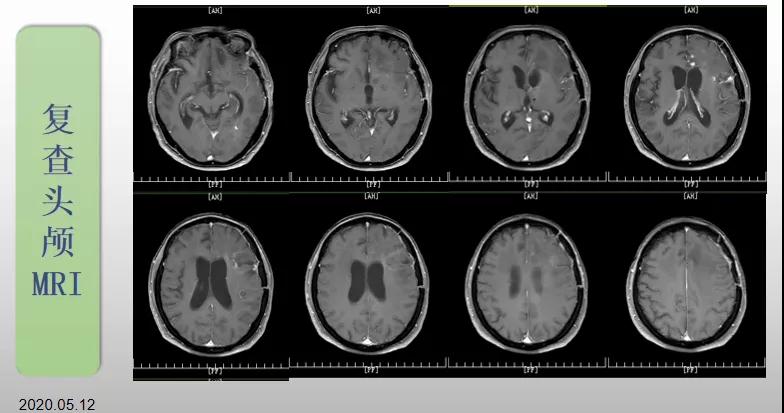

綜合治療 電場(chǎng)治療助70歲患者回歸正常生活

70歲的郝女士去年曾在外院查出“左額島葉”膠質(zhì)母細(xì)胞瘤(WHO Ⅳ級(jí)),并做了左側(cè)額島葉占位性病變切除術(shù)。術(shù)后進(jìn)行了同步放化療。由于治療條件有限,郝女士慕名來到我院就診。賀世明主任率領(lǐng)醫(yī)護(hù)團(tuán)隊(duì)立即為郝女士進(jìn)行了全面的檢查,決定為其進(jìn)行綜合治療 電場(chǎng)治療。經(jīng)過三個(gè)多月的綜合治療,患者復(fù)查頭顱MRI病變較前明顯縮小。出院時(shí),郝女士神志清醒,睡眠飲食正常,說話很流利?!拔沂翘芍M(jìn)來的,現(xiàn)在不用人攙扶,自己就可以走出病房了?!焙屡坷t(yī)護(hù)人員的手說。